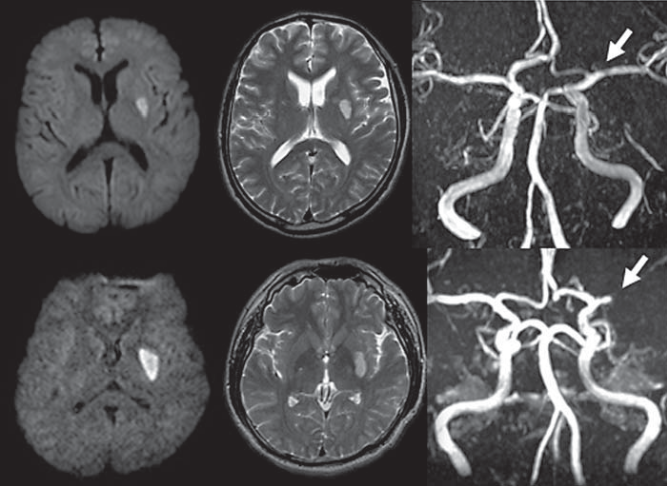

腔隙性脑梗死这个临床诊断,可以慢慢作古了

腔隙性脑梗死患者头部核磁共振影像学特点分析